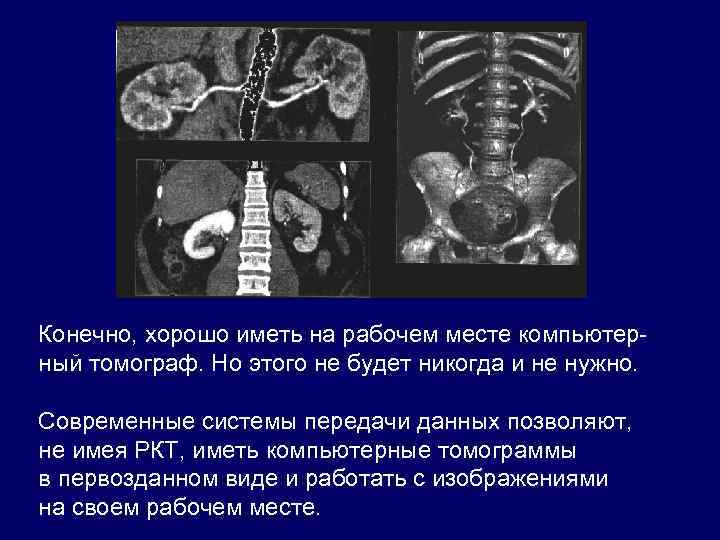

Конечно, хорошо иметь на рабочем месте компьютерный томограф. Но этого не будет никогда и не нужно. Современные системы передачи данных позволяют, не имея РКТ, иметь компьютерные томограммы в первозданном виде и работать с изображениями на своем рабочем месте.